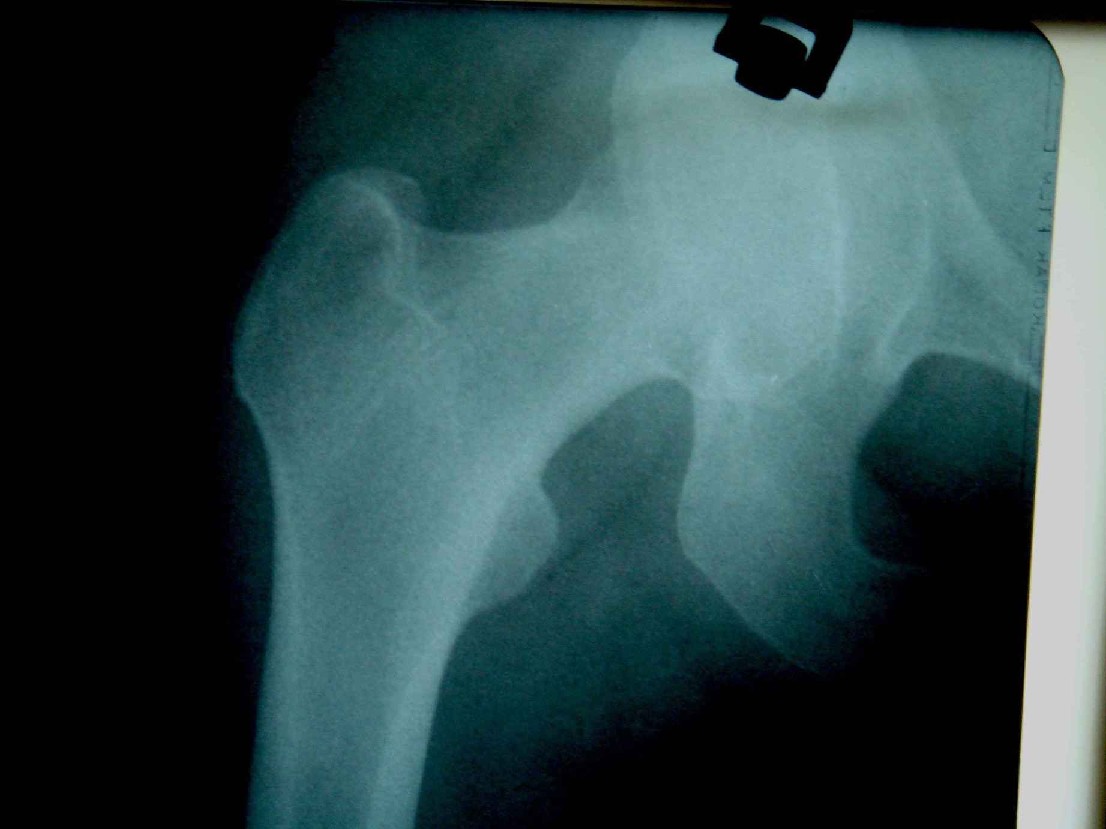

患者,女,因外伤就诊。摄骨盆及右股骨。当时报告骨盆未见明显异常,右股骨中段粉碎性骨折。五天后行股骨中段骨折内固定手术,术中摄床边片示股骨颈骨折。现把术前和术中图像上传。请大家高诊,分析股骨颈骨折是术前漏诊还是其他原因。术前骨盆片右股骨颈显示欠佳是由于股骨中段骨折无法将股骨颈完全显示。

术前片示右股骨颈未见明显骨折征象。如果事先有骨折,由于投照位置原因,骨折线也是完全有可能被挡住重叠而看不见的(并且本例骨折对位良好,更有可能看不到)。所以要凭此判断述前是否有骨折不容易

从上传的照片来看,术前无法诊断骨折。可能是投照角度的问题。

由于术前下段骨折 股骨颈显示不完全所致 很正常啊

术前股骨颈未见骨折

当然可能由于术前骨折对位对线良好,有可能观察不到骨折线,有的裂纹骨折平片当时是看不见骨折线的,7天左右才可能由于骨折线水肿&活动等原因从而显示出骨折线;还有投照位置的原因。术前未看见骨折线也属正常现象。

考虑术前骨折(由于投照位置原因,骨折线有可能被挡住重叠而看不见的或骨折处未有移位可能看不到)。术后由于外力作用骨折线增宽而清楚显示)。

术前由于位置原因使股骨颈未全部显示,骨折线与股骨头重叠,骨折也可以使股骨颈缩短

回头看术前片,可见一低密透光区.

术前所照的片子体位好象有点不标准,右侧股骨颈显示不是很好,没有完全展开,所以不好说术前就一定没有骨折的情况.

楼主给我们大家提供了非常好的片子,感谢!该片股骨颈的骨折术前看不到骨折。这个和体位也有关,但是我们都知道,那些标准的体位是给健康人设计的,外伤比较重的往往都无法标准投照。不知道同行们有没有这样一种感受:发现明显的问题了,就心里比较踏实了,舒坦了,就不容易对其它细节仔细观察了。如果没有发现明显的问题,就仔细的翻来覆去的看。所以这个片子给我们很大的教训:仔细阅片!即便是已经发现问题了。如果非要给鸡蛋里面挑骨头,我认为楼主忽略了右髋关节囊的肿胀,诊断报告应该提一下。外伤的病人我最怕股骨颈的漏诊,一般我都要看软组织。我是一个小医院的,我深有感触,发现骨折不是功劳,而漏诊却是事故,还遭受别人耻笑:放射科的连骨头断没断都看不出来!

关于楼主说的骨折线的形态,的确和一般外伤的有种不太一样的感觉,上方裂隙较明显,下方骨皮质“连续”,我认为成年人应该是全部断了的,不全骨折的可能性非常非常小,该片恰好无法全部显示骨折线。骨折线的形态不能判定术前还是术后骨折。以上只是个人小小看法,请各位老师指正为谢!